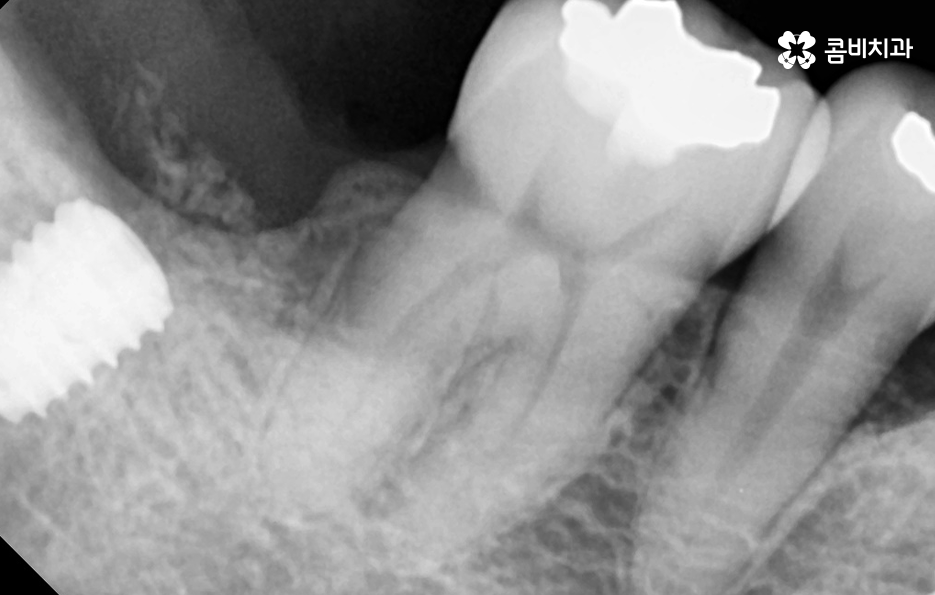

우리가 보편적으로 생각하게 되는 임플란트 치료기간의 경우 치아 하나를 상실하고 임플란트를 1:1로 치료할 때 예상 기간에 대해서 고려하게 되는 경우가 기본적인 접근 방법이라면 실질적으로 치과에서 임플란트를 하게 되는 연령대를 보더라도 보통 50대에서 60대 이후에 치아를 상실하게 되는 환자분들이 급증하기 때문에 위 사진의 사례처럼 여러 치아를 상실하고 임플란트를 식립하게 되는 경우도 많을 거예요